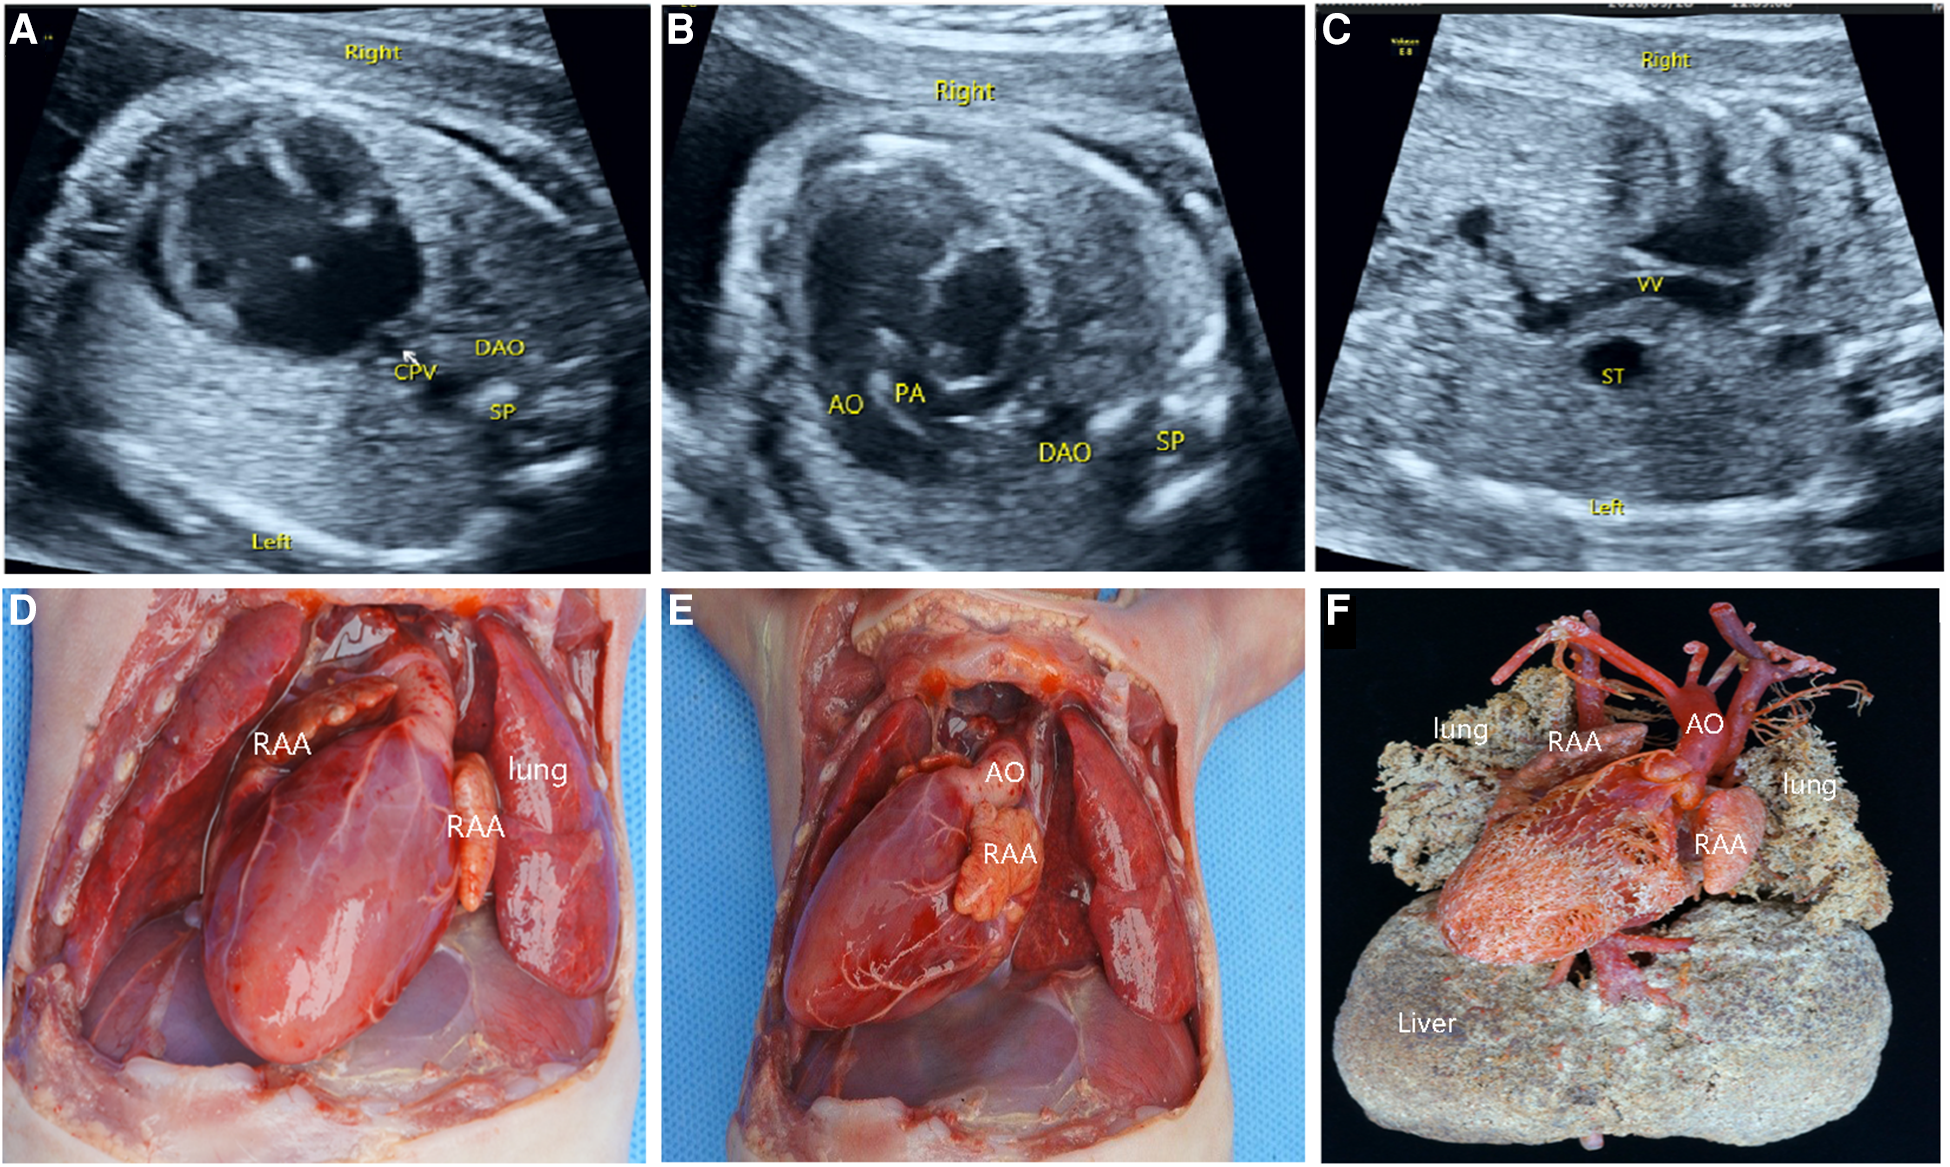

Figure 4

Prenatal ultrasonography and anatomical and vascular casting images of RI fetuses. (A) the “+” cross in the center of the heart disappeared during diastole in the four-chamber view, which was a complete endocardial cushion defect. (B) Common pulmonary vein entered the portal vein downwards via the descending vertical vein. (C) AO and pulmonary artery from the right ventricle. Figure (D–F): Front view of the specimen: right-sided heart, midline liver, bilateral right atrial appendage, aorta emanating from the front of the ventricle, left aortic arch, pulmonary artery at the rear, and double superior vena cava were seen. The back view of the specimen: four pulmonary veins formed a common pulmonary vein and flowed downwards via the descending vertical vein to the portal vein. CPV, a common pulmonary vein; VV, descending vertical vein.

Anatomy and casting characteristics of fetal right isomerism

Of the 46 terminated cases, 41 cases received autopsy, which confirmed the prenatal diagnosis, and 5 cases underwent vascular casting. The typical malformations of RI included the right heart, bilateral right atrial appendages (Figure 4D), and APVC (Figures 4E,F). The combined intracardiac abnormalities included AVSD, single atrium, single ventricle, double-outlet right ventricle, and pulmonary arterial stenosis or atresia, etc. The extracardiac malformations included gastric blisters on the right side and the posterior part of the abdominal cavity near the spinal column, the abdominal aorta and IVC arranged on the same side of the spine (Figure 4E), bilateral lungs with three lobes, midline liver (Figure 4F), and asplenia. Atypical signs included one case (2%) of gastric vesicles located in the center of the posterior part of the abdominal cavity and partially herniated into the thoracic cavity, four cases (7%) of a small, thin spleen at the back of the stomach, two cases (4%) of bilateral lungs with four lobes, five cases (9%) of the small left atrial appendage of unclear morphological features, and one case (2%) of double superior vena cava with bridging vein connection.